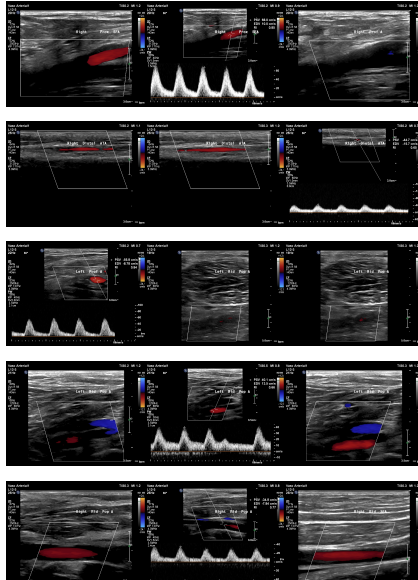

Relevant Test Results Prior to Catheterization

ABI measured on December 13, 2021, was 0.64on the right and 0.59 on the left. Duplex ultrasonography performed on August6, 2024, revealed monophasic flow in bilateral CFA, SFA, popliteal, ATA, andPTA arteries, favoring bilateral severe iliac artery disease. Subsequent CTangiography on November 15, 2024, demonstrated aortoiliac occlusive disease,without evidence of aneurysm or distal vessel obstruction. Laboratory databefore admission showed HbA1c 6.9% and LDL 76 mg/dL.

Diagnosticangiography revealed total occlusion of both common iliac arteries, while theexternal iliac arteries remained patent bilaterally. The lesions wereconsistent with aortoiliac occlusive disease (Leriche syndrome), and the distalflow was preserved via collateral circulation.